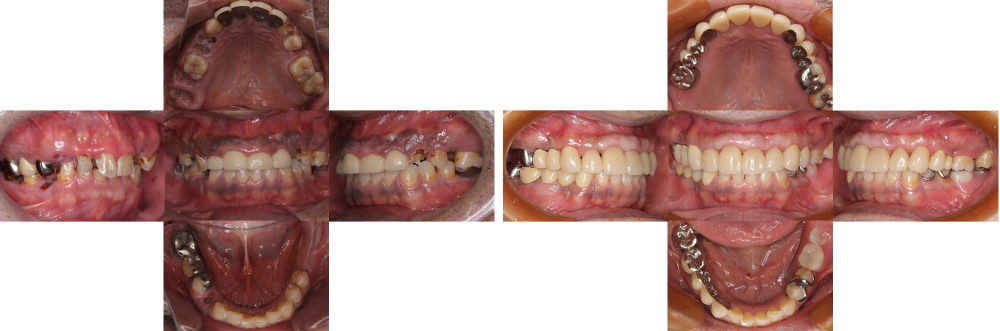

全顎保険治療

術前

術後

| 治療内容 | 全顎的に咬合再構成を行い保険内で治療を行った |

|---|---|

| 治療期間・回数 | 約4年・約50回 |

| 費用 | 保険適用となります |

| リスク・副作用 |

|

| 治療内容 | 全顎的に保険内で治療を行った |

| 治療期間・回数 | 約3年・約60回 |